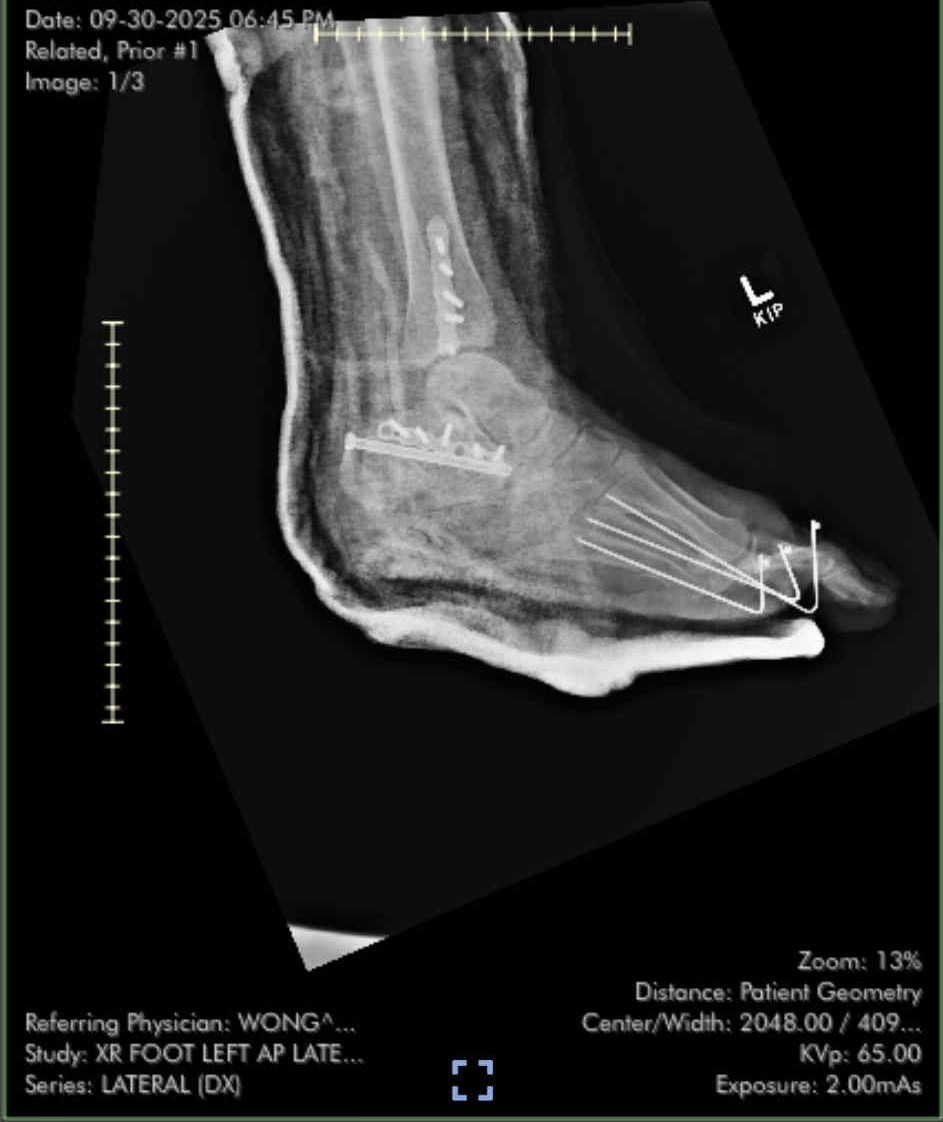

Our dear friends’ son, Holland, was on his motorcycle when he was broadsided by a car in a terrible accident that severed his foot. Surgeons managed to reattach it, but it’s still uncertain whether it can be saved — and he will require multiple additional surgeries if he’s able to keep it. He now faces months of surgeries, rehabilitation, and recovery — and is devastated beyond belief.